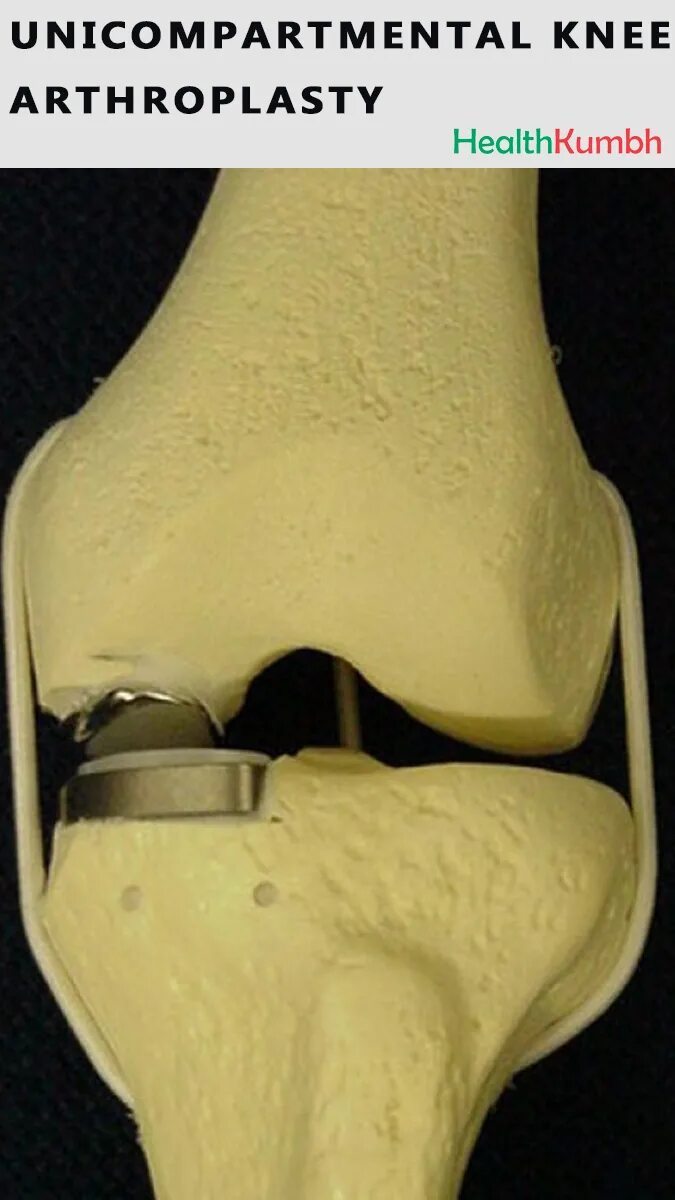

Эндопротезирование коленного после операции сколько болит